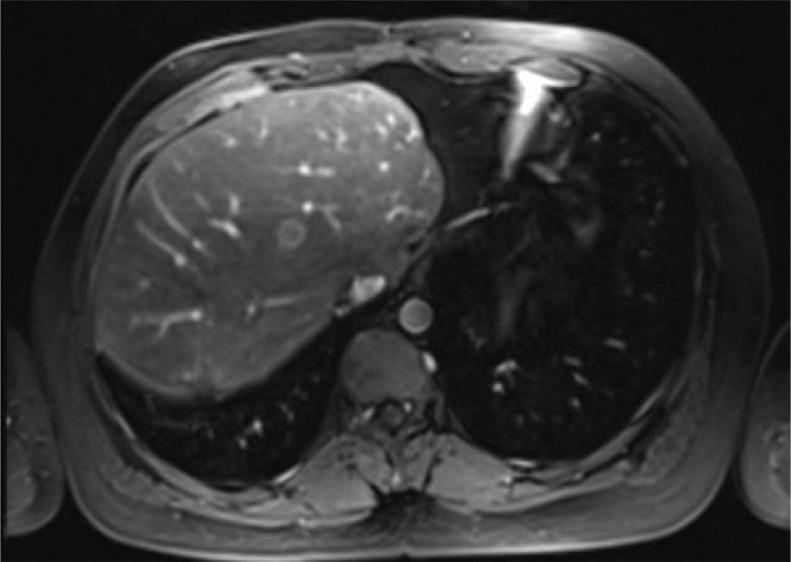

Nested stromal epithelial tumor (NSET) of the liver is an extremely rare and unusual liver neoplasm with limited evidence of best practice for management. We report a 28-year-old male with NSET managed with primary partial hepatectomy with subsequent disease recurrence with follow-up metastectomy and successful radiofrequency ablation (RFA). Management of NSET of the liver requires a multidisciplinary approach. RFA proves beneficial in a patient with disease recurrence following tumor resection. In order to validate the regular use of RFA, more long term studies would be required.

肝脏巢状间质上皮肿瘤(NSET)是一种极其罕见且不寻常的肝脏肿瘤,关于其最佳治疗方法的证据有限。我们报告了一名28岁的NSET男性患者,接受了一期部分肝切除术,随后疾病复发,进行了后续的转移灶切除术和成功的射频消融(RFA)。肝脏NSET的治疗需要多学科方法。对于肿瘤切除后疾病复发的患者,RFA被证明是有益的。为了验证RFA的常规使用,还需要更多的长期研究。